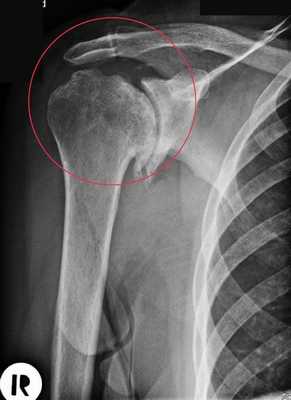

Адгезивный капсулит дифференцируют с артритом, ревматической полимиалгией, хондроматозом, асептическим некрозом головки плеча, синдромом Милуоки и злокачественными опухолями. В ходе дифференциальной диагностики назначают анализ на С-реактивный белок, определяют СОЭ, выполняют рентгенографию. По данным лабораторных исследований изменения отсутствуют, на рентгенограммах при длительном течении может обнаруживаться остеопороз.

Артроз плечевого сустава на рентгене.